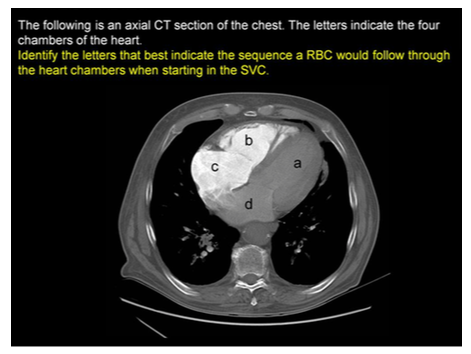

CBDA